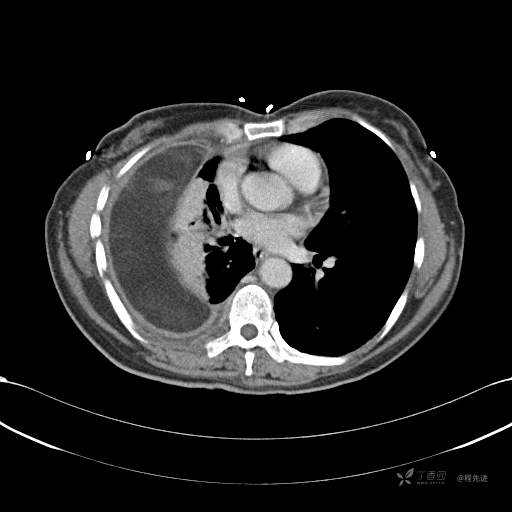

患者性别:女

患者年龄:51岁

简要病史:胸闷半年